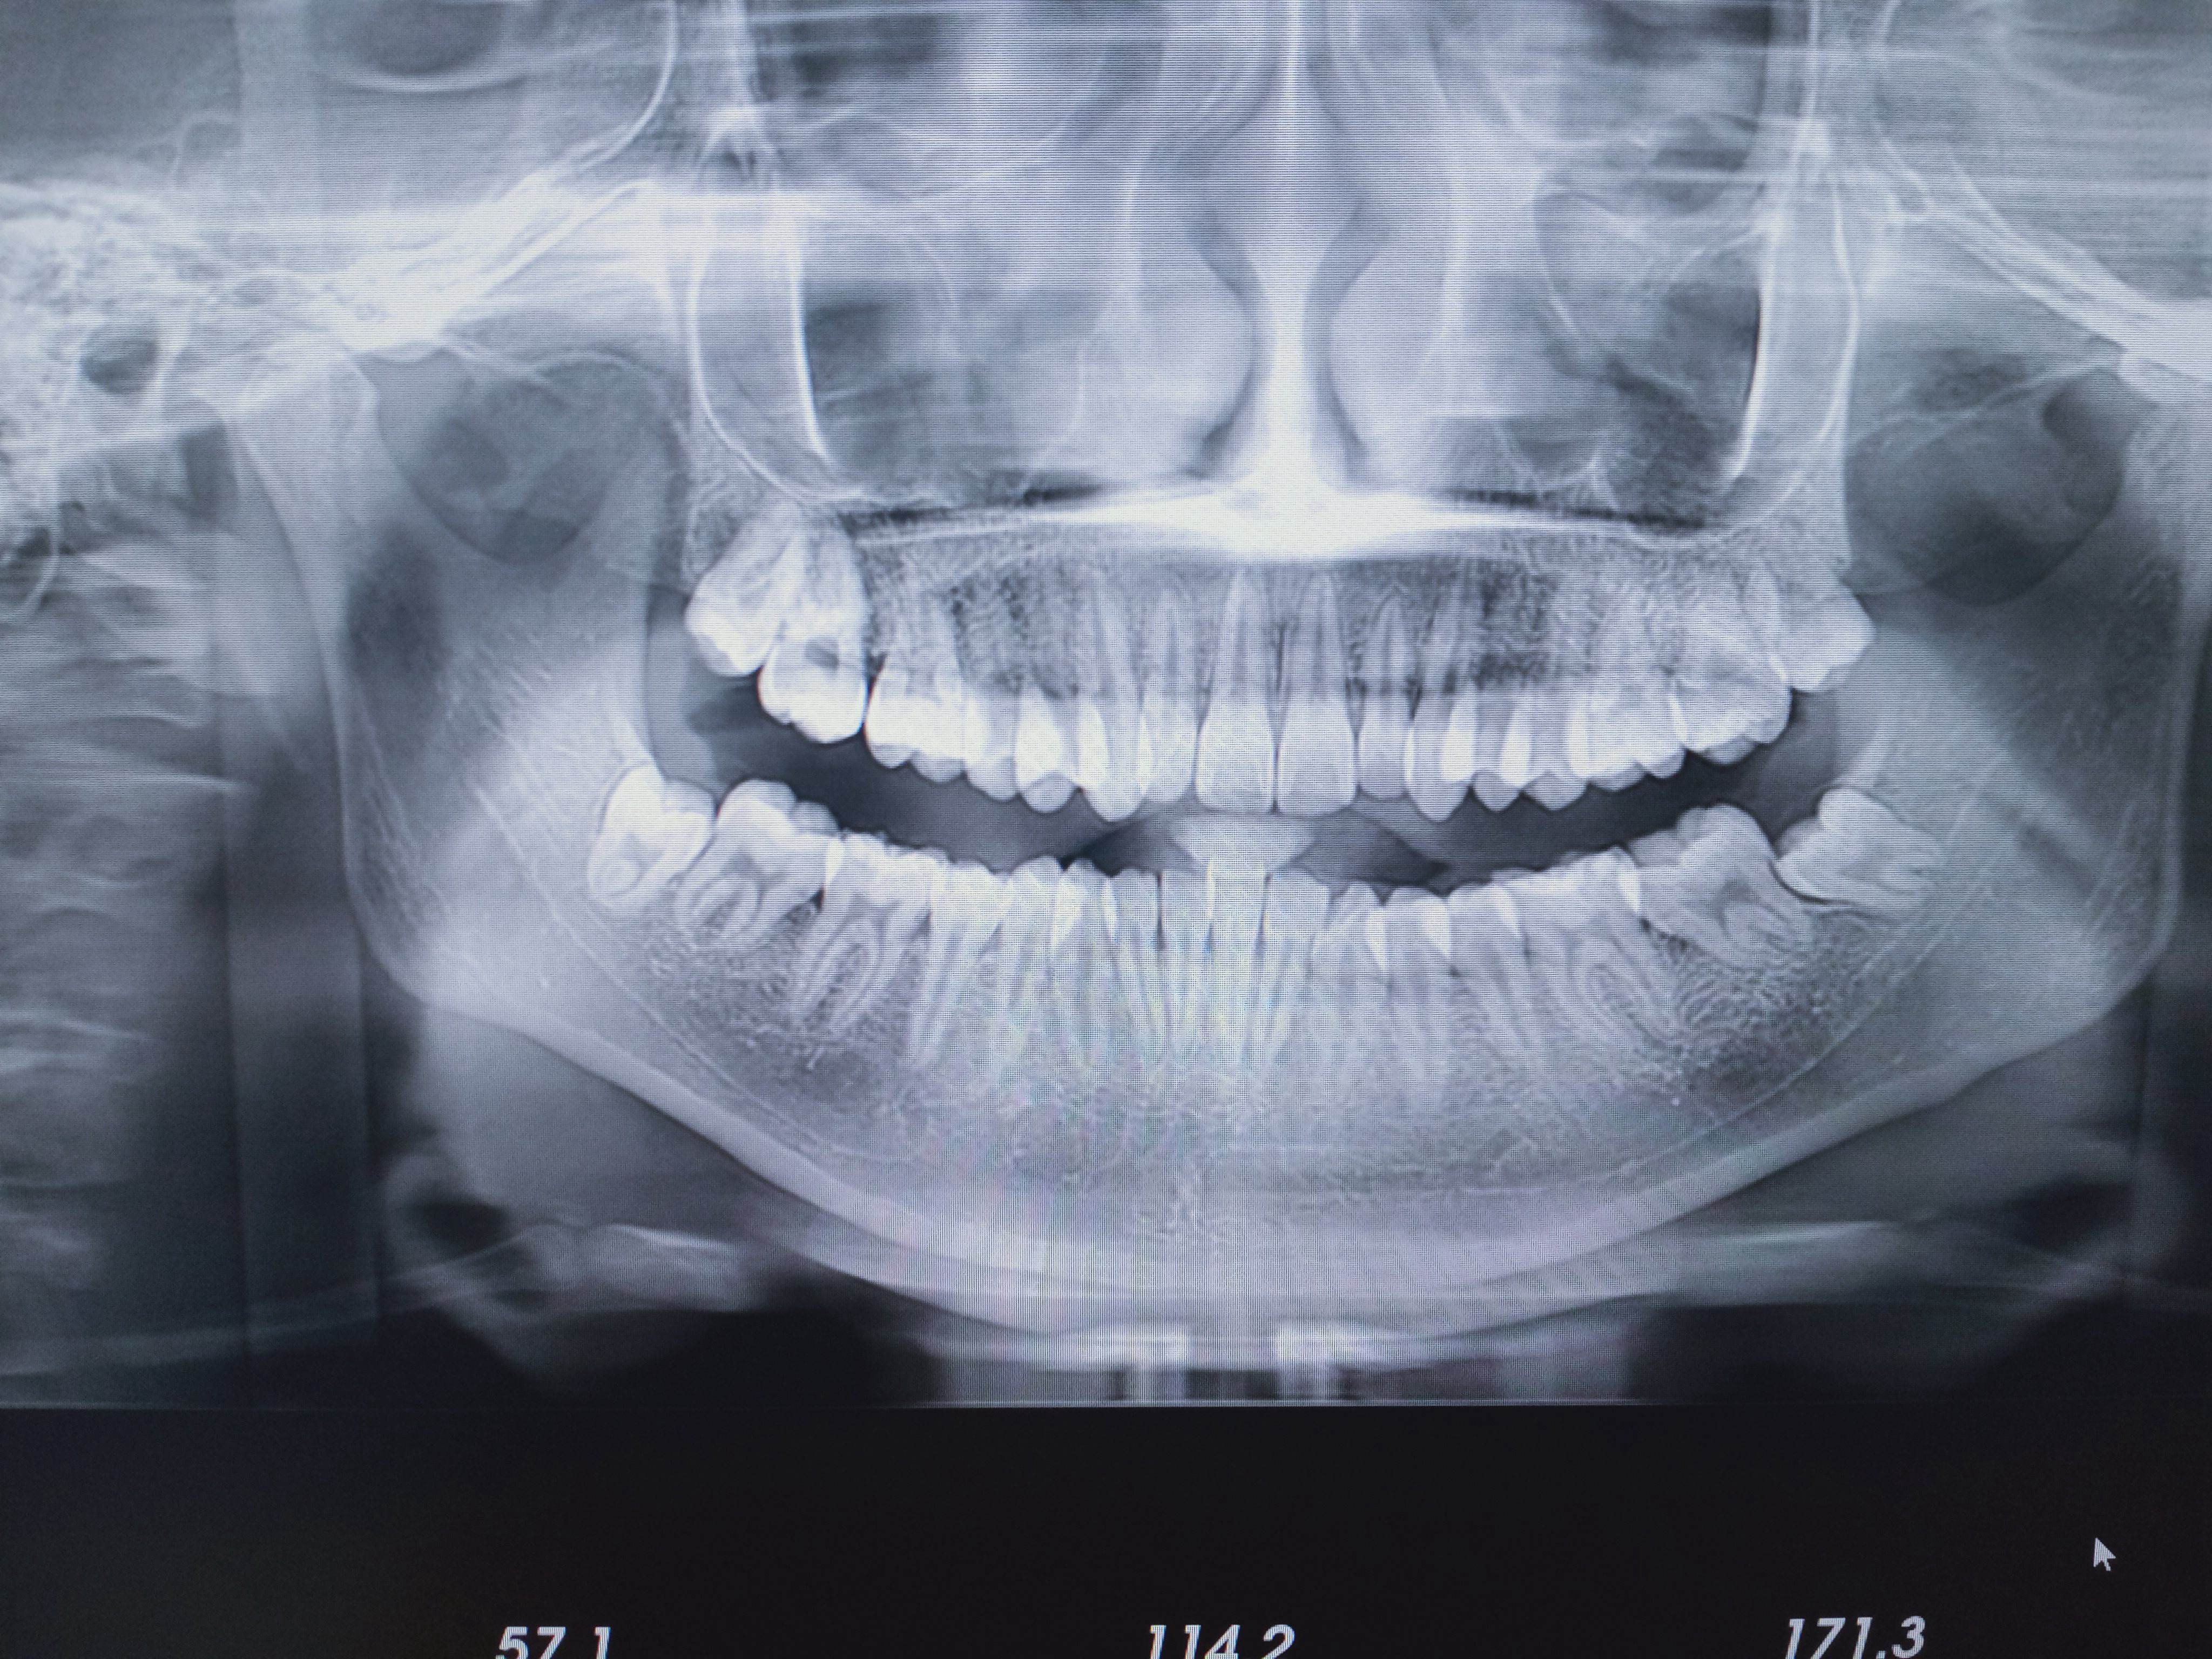

1、全景片(曲面断层片):适用于观察全口牙的健康状况、上下颌骨肿瘤、外伤、畸形、全口牙槽骨吸收程度,以利于检查出肉眼无法观察到的病损。